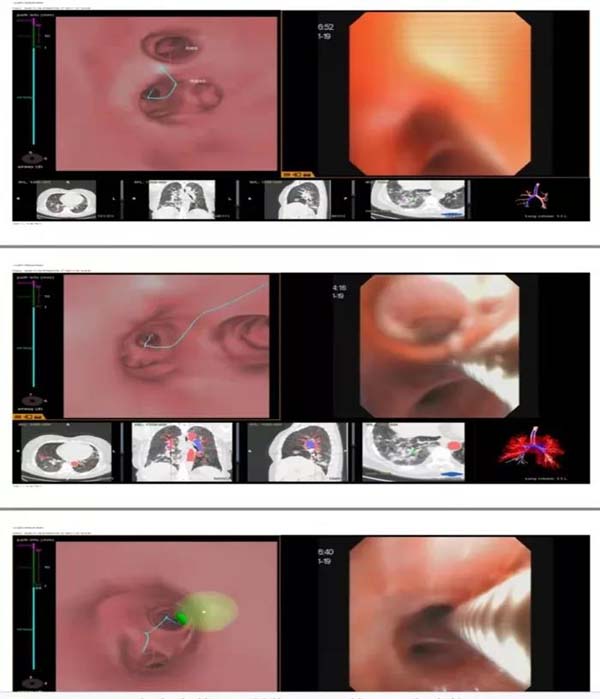

1、无痛支气管镜检查:通过支气管镜检查可观察肿瘤的部位、范围,钳取或刷取病变部位组织、细胞作病理学检查,全肺到达。

2、经皮肺穿刺活检:引导的方法有X线透视、CT或B超等辅助下完成,而应急总医院呼吸与危重症医学科/肿瘤内科2部在该技术的准确率可达90%-95%,依托本院病理科知名专家,科室诊断准确率可达85%-90%以上。

3、多学科/多技术综合优势,并可实现诊断与治疗“一条龙”服务,使肺结节患者得到更加规范、便捷、准确地诊疗。

医生会根据患者的具体情况应用相应的检查手段,如低剂量CT、AI辅助诊断系统、多学科会诊,必要时通过经皮穿刺、经支气管镜等方式进行病理活检,以及同步活检、手术切除等方法。

肺结节的鉴别诊断具有较强的专业性,对检查设备和程序也有很高要求。肺结节专科门诊可为患者提供专业的检查、多学科会诊及系统随诊,包括同等专业扫描模式下的影像学比对、精准的支气管镜检查、病理检查、丰富专业的微创治疗方式选择,以及涉及外科、微创等多学科、多种治疗方案中提供合理建议。